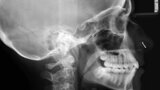

Ortodontická léčba komplexních případů malokluze pomocí průhledných alignerů